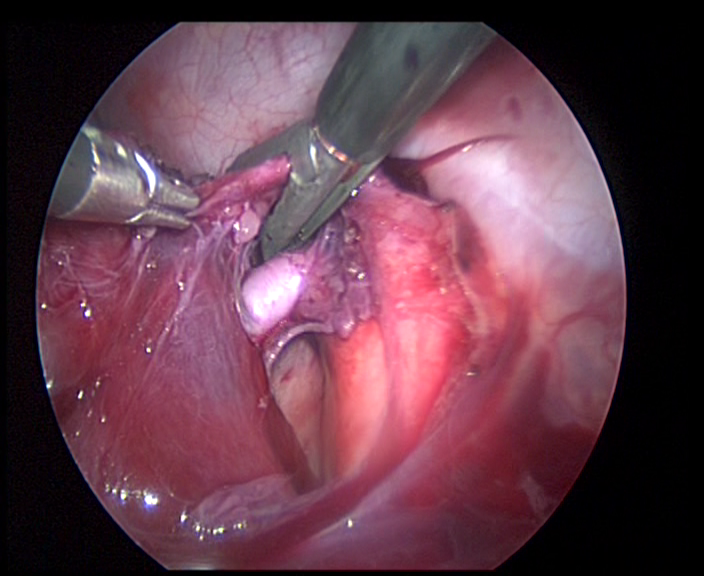

La chirurgia mini invasiva

|

Figura 10. Toracoscopia13 |

Figura 11. Toracoscopia |

Figura 12. Aspetto toracoscopio di resezione lobare inferiore destra. |

Figura 13: Risultato cosmetico a 1 anno. |